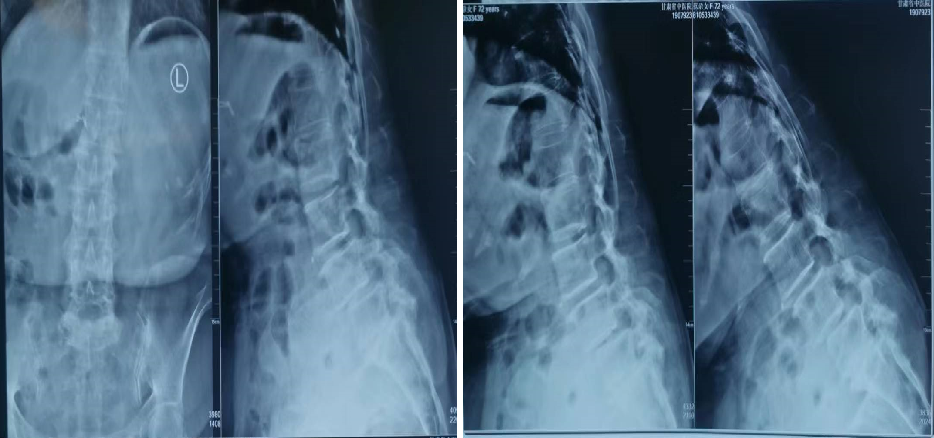

胸腰椎爆裂性骨折的影像学诊断!